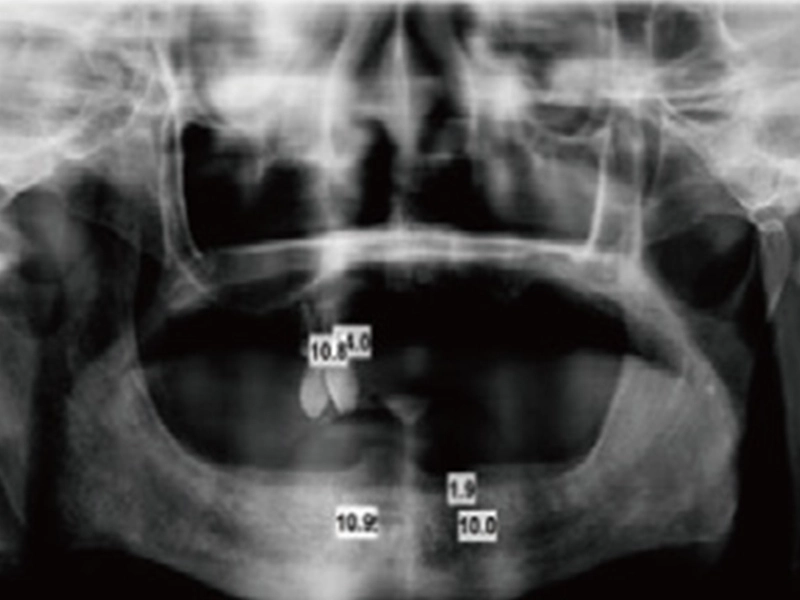

1. Röntgen nehmen

Nehmen Sie Röntgenaufnahmen und entscheiden Sie den Platzierung sort für die Zahn implantate.